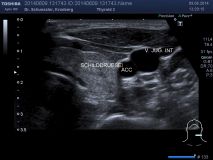

Farbkodierte Ultraschalluntersuchung der Schilddrüse

Mit dieser Untersuchung lassen sich die Schilddrüsengröße, ihre Struktur und auch Knoten, Zysten oder entzündliche Veränderungen sichtbar machen. Durch Hinzunahme der Farbkodierung lässt sich auch die Durchblutungssituation der Schilddrüse sichtbar machen.